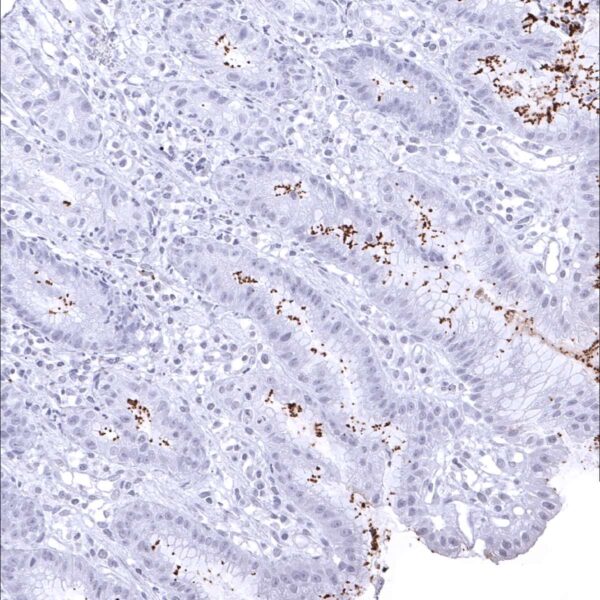

Positive control = Gastric tissue with known helicobacter pylori infection should show a distinct staining of bacteria on the surface and/or within glands.

Negative control = Gastric tissue: Normal epithelial and stromal cells should not stain.

Among normal adult tissues, immunostaining is not observed for the helicobacter specific antibody MSVA-466M.